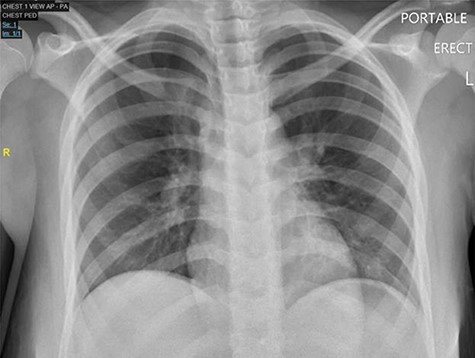

The patient was taken to the operating room for diagnostic laparoscopy. A 4-mm perforated duodenal ulcer by the pylorus with leaking bile was found and repaired with an omental patch. On postoperative Day (POD) 3, an upper gastrointestinal study was done, which showed no signs of obstruction or leak (Fig. 2). Serum gastrin levels were reported normal. On POD 4, he was started on a diet. He tested positive for Helicobacter pylori and was therefore treated with eradication triple therapy (proton pump inhibitor, amoxicillin and clarithromycin). The patient recovered uneventfully and was discharged home on POD 7, and was symptoms free at follow-up.

Upper gastrointestinal series (a)/small bowel follow-through (b): normal stomach demonstrated. Normal duodenum and proximal jejunal loops. No contrast extravasation identified. Oral contrast in the distribution of stomach, duodenum and proximal jejunal loops with no evidence for extravasation.